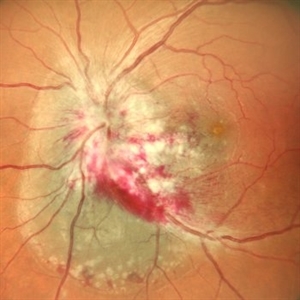

Subretinal Bleed

A 60 YEAR OLD FEMALE PRESENTED WITH COUNTING FINGERS VISION FROM A SUB-RETINAL HEMORRHAGE AT THE MACULA. OCT SHOWS VARIABLE SUB -RETINAL FLUID. PARS PLANA VITRECTOMY WITH DRAINAGE OF THE SUB-RETINAL BLOOD WAS PERFORMED. POST-OPERATIVE OCT SHOWS NO SUB-RETINAL FLUID WITH VARIABLE OUTER RETINAL CYSTIC CHANGES AND VISUAL ACUITY IMPROVING TO 20/120.

Photographer: Dr. Akansha Sharma-Retina Foundation, Ahmedabad

Condition/keywords: subretinal hemorrhage, subretinal blood